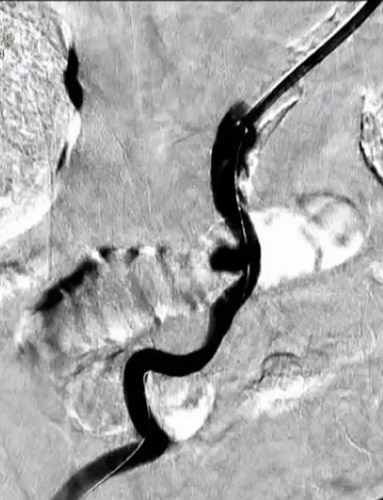

主訴は右足跛行(Ratherford3)、既往歴は高血圧、糖尿病、脂質異常症、心房細動であり、右CIA閉塞病変の治療を行うこととしたがEIAに動脈瘤があった(瘤部の血管径は約10mm)(図1、図2)。

左dRAからエコーガイド穿刺を行いGlidesheateh Slender7FrとR2P SlenGuideの組み合わせでアプローチを開始した。その際、カバードステント(シャフト長135cm)の留置を予定していたため、よりガイディングカテのシステム全長を短くするためにR2P SlenGuideに止血弁を組み合わせた。R2P SlenGuideが病変部に対してコアキシャルになり難く、バックアップは十分に取れなかったが、6gワイヤー(0,014“)で病変を通過後、Navifocus WRでintra-plaque内であることを確認し、Senri 3-40mm でプレ拡張を行った(図3)(図4)。